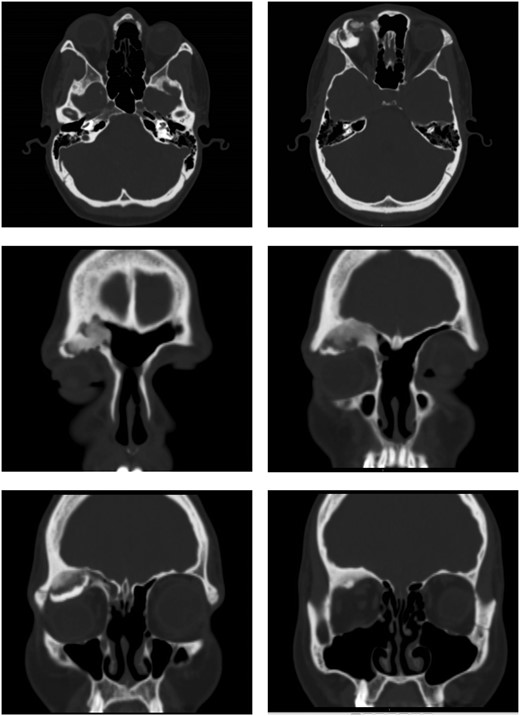

Post-operatively, the patient recovered well with no complications. Examination of the eye four weeks after surgery showed significant improvement—visual acuity was 6/6 on the right, 6/5 on the left. The visual acuity improved to 6/6 on both sides 10 months after surgery; however, there was a residual hypotropia. A repeat CT scan at 4 months post-surgery displayed no bulky residual disease and improvement of proptosis (Fig. 3).

Repeat CT scan at 4 months after surgery, demonstrating no residual disease and radiological improvement of proptosis.